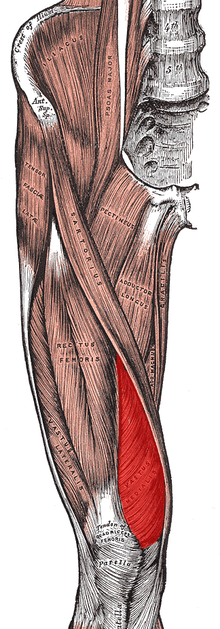

- Quadriceps muscle imbalance[2]

The majority of exercise programs intended to treat PFPS are designed to strengthen the quadriceps muscles.[4] Emphasis during exercise may be placed on coordinated contraction of the medial and lateral parts of the quadriceps as well as of the hip adductor, hip abductor and gluteal muscles.[4] Many exercise programs include stretches designed to improve lower limb flexibility.[4] Electromyographic biofeedback allows visualization of specific muscle contractions and may help individuals performing the exercises to target the intended muscles during the exercise.[4] Electrostimulation may be used to apply external stimuli resulting in contraction of specific muscles and thus exercise.[2]

A 2011 systematic review stated that evidence supports the use of quadriceps exercise for managing patellofemoral pain syndrome and that quadriceps strengthening is considered to be the "gold" standard treatment for patellofemoral pain syndrome.[9] Quadriceps strengthening is commonly suggested because the quadriceps muscles help to stabilize the patella. Quadriceps weakness and quadriceps muscle imbalance may contribute to abnormal patellar tracking.[9] If the strength of the vastus medialis muscle is inadequate, the usually larger and stronger vastus lateralis muscle will pull sideways (laterally) on the kneecap. Strengthening the vastus medialis to prevent or counter the lateral force of the vastus lateralis is one way of relieving PFPS. Moderate evidence supports the addition of hip abductor and external rotator strengthening, as well as exercises targeting hip flexion and hip extension.[9][13][13] When executing these exercises, proper form is very important in order to ensure that the musculature is activated in such a way that will not lead to further injury. Inflexibility has often been cited as a source of patellofemoral pain syndrome. Stretching of the laterial knee has been suggested to help.[14]